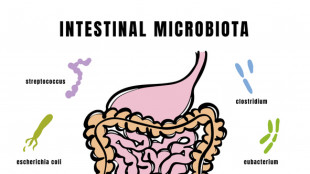

Con il latte materno si trasferiscono i batteri 'buoni' nel microbiota dei neonati

Lo studio sull'impatto dell'alimentazione delle madri, osservata continuità biologica

Il microbiota intestinale si compone già nei primi mesi di vita

Studio Campus Bio-medico-B.Gesù, da latte materno le prime tracce della salute futura